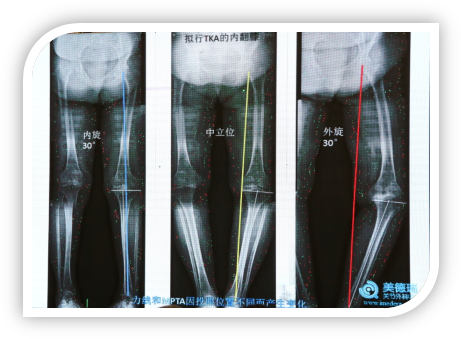

下图患者因内侧磨损做膝关节置换,中立位膝关节力线在内侧,在内旋位时膝关节正常,但在外旋位的时候膝关节力线内移情况非常严重,完全有可能因为影像学误判造成的。其实患者自然位占立时内翻很厉害,是因为屈曲畸形,为了站直不得不外旋,增加了内翻的错觉。

image014.png

image015.png

目前,很多HTO被用于膝关节炎内侧间隙磨损形成的关节内内翻畸形,这就带来了一个问题,很多人的片子MPDA是正常范围,因为内侧关节肌肉磨损做了HTO,为了使力线外移,做了截骨以后人为造成了胫骨近端的关节外畸形,蔡谞教授指出在临床上这样的病例非常多。